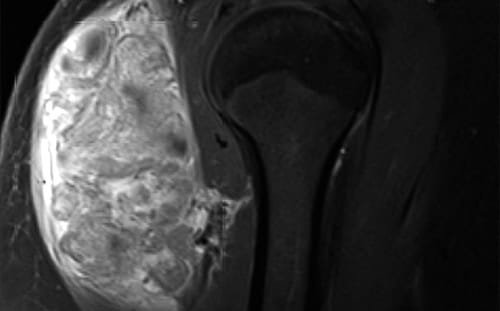

When a tumor of musculoskeletal tissue is cancerous, it is called sarcoma. It is the job of the orthopedic oncologist to diagnose these tumors and determine if they have spread.

In addition to sarcoma, orthopedic oncologist also treat lymphoma, multiple myeloma and metastatic cancers that come from other areas of the body such as the breast, lung, prostate, kidney and thyroid gland. Orthopedic oncologists are crucial contributors to the treatment plan for these patients as they can provide treatment options that have the potential to greatly improve quality of life. Orthopedic oncologists also treat non-cancerous tumors of the musculoskeletal system such as lipomas, neurovascular tumors, bone cysts, fibrous tumors and many others.